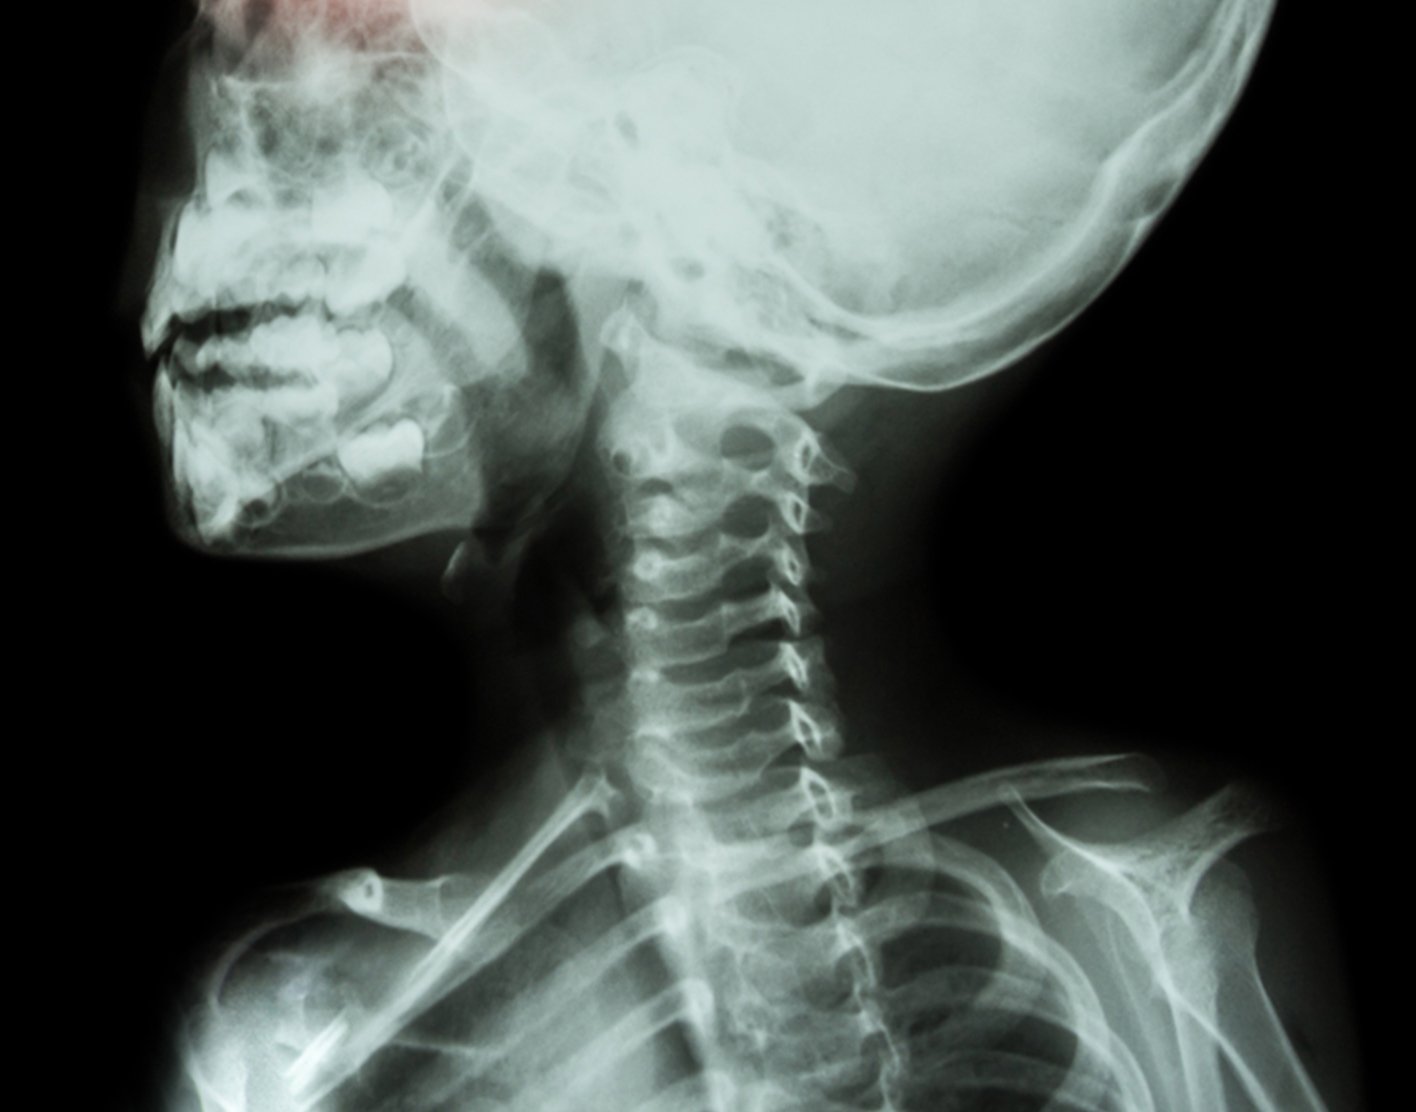

X-ray - skeleton

Structures that are dense (such as bone) will block most of the x-ray particles. These areas will appear white. Metal and contrast media (special dye used to highlight areas of the body) will also appear white. Structures containing air will be black. Muscle, fat, and fluid will appear as shades of gray.